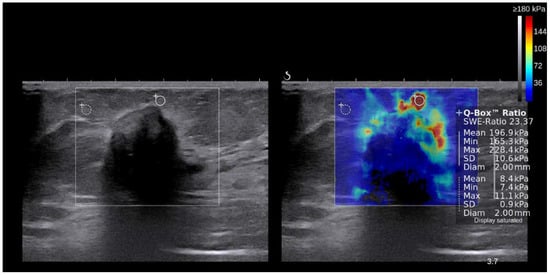

2.2. Shear Wave Elastography

| Elasticity value (kPa, mean ± SD) | |

| Mean | 155.0± 69.4 |

| Minimal | 122.9± 95.2 |

| Maximal | 176.1± 76.3 |

| Ratio | 13.5 ± 11.6 |